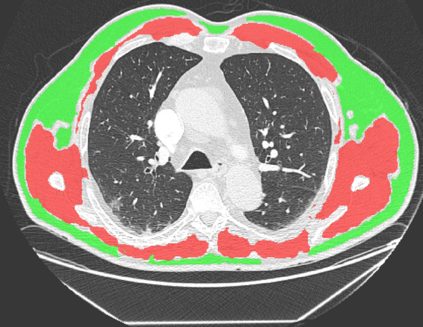

The COVID-19 pandemic has had a considerable impact on day-to-day life. Tackling the disease by providing the necessary resources to the affected is of paramount importance. However, estimation of the required resources is not a trivial task given the number of factors which determine the requirement. This issue can be addressed by predicting the probability that an infected patient requires Intensive Care Unit (ICU) support and the importance of each of the factors that influence it. Moreover, to assist the doctors in determining the patients at high risk of fatality, the probability of death is also calculated. For determining both the patient outcomes (ICU admission and death), a novel methodology is proposed by combining multi-modal features, extracted from Computed Tomography (CT) scans and Electronic Health Record (EHR) data. Deep learning models are leveraged to extract quantitative features from CT scans. These features combined with those directly read from the EHR database are fed into machine learning models to eventually output the probabilities of patient outcomes. This work demonstrates both the ability to apply a broad set of deep learning methods for general quantification of Chest CT scans and the ability to link these quantitative metrics to patient outcomes. The effectiveness of the proposed method is shown by testing it on an internally curated dataset, achieving a mean area under Receiver operating characteristic curve (AUC) of 0.77 on ICU admission prediction and a mean AUC of 0.73 on death prediction using the best performing classifiers.